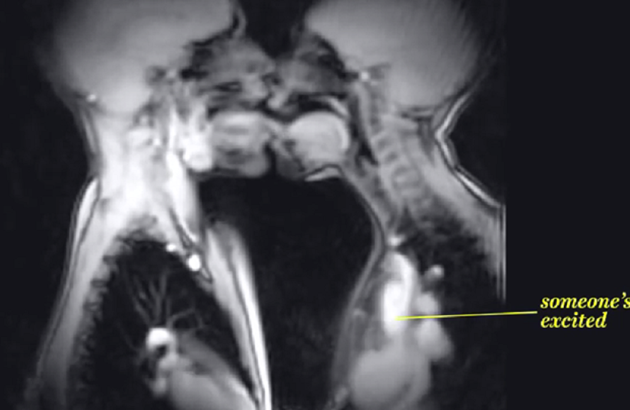

Da bi se organizam uzbudio potrebno je između 10 i 30 sekundi. Krv nam tada jurne u genitalije. Muškarcu se ukruti penis, a ženama vagina počinje da vlaži.